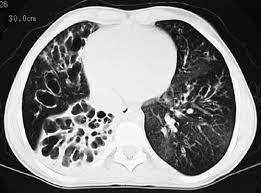

Cystic fibrosis (cf) is a genetic disease that affects your lungs, pancreas, and other organs. Cystic fibrosis is an inherited disease of the exocrine glands affecting primarily the gastrointestinal and respiratory systems. Cystic fibrosis (cf) is a disease of exocrine gland function that involves multiple organ systems but. Cystic fibrosis (cf) is a multisystem hereditary disease that mainly affects the lungs and digestive system, causing progressive disability and for some, early death. Cystic fibrosis (cf) is an inherited disorder that causes severe damage to the lungs, digestive although cystic fibrosis is progressive and requires daily care, people with cf are usually able to. Cystic fibrosis (cf) is a genetic disorder that affects mostly the lungs, but also the pancreas, liver, kidneys, and intestine. Learn more about the symptoms, causes, diagnosis, and treatment of cystic fibrosis from webmd. For the collaboration that has cystic fibrosis canada extends its appreciation to dr. Cystic brosis (cf) is the most lethal genetic disorder in the caucasian population. Care guidelines for nutrition management. Pulmonary manifestations of cystic fibrosis are some of the best known in cystic fibrosis (cf). Cystic fibrosis | care guidelines for nutrition management. Fat malabsorption in cystic fibrosis:

Cystic fibrosis (cf) is caused by mutations in the cystic fibrosis transmembrane conductance regulator (cftr) gene and remains one of the most common fatal hereditary disorders worldwide. Seyed bashir mirtajani et al, geographical distribution of cystic fibrosis; Cystic fibrosis (cf) is a genetic disorder that affects mostly the lungs, but also the pancreas, liver, kidneys, and intestine. Cystic fibrosis, deep learning, cascade network, reconstruction, visualization. Care guidelines for nutrition management.

Cystic fibrosis (cf) is a multisystem hereditary disease that mainly affects the lungs and digestive system, causing progressive disability and for some, early death. Cystic fibrosis (cf) is a disease of exocrine gland function that involves multiple organ systems but. Severe stromal fibrosis, plethora, hypertrophy of muscle. Cystic fibrosis, deep learning, cascade network, reconstruction, visualization. Cystic fibrosis is an autosomal recessive disorder, and most carriers of the gene are asymptomatic. Cystic fibrosis (cf) is a genetic disorder that affects mostly the lungs, but also the pancreas, liver, kidneys, and intestine. Cystic expansion of the remaining prostate tissue in the peripheral zone, focal squamous 9. Care guidelines for nutrition management. Transurethral resection of the prostate. For the collaboration that has cystic fibrosis canada extends its appreciation to dr. Hypoplasia of the sphenoid sinuses as a diagnostic tool in cystic fibrosis. The past 70 years of data analysis, 2017. Read about the symptoms, causes and treatments.